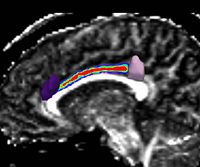

- We have started the project of investigating Arcuate Fasciculus using Stochastic Tractography (Figure 6). This structure is especially important in both VCFS and schizophrenia, as it connects language related areas (Brocka and Wernicke's), and is involved in language processing quite disturbed in schizophrenia patients. It also can not be reliably traced using deterministic tractography. Progress:

- Whole brain segmentation, and automatic extraction of regions interconnected by Arcuate Fasciculus (Inferior frontal and Superior Temporal Gyri). This step has been accomplished for the entire dataset of 23 schizophrenia subjects and 23 controls.

- White matter segmentation, in order to prevent algorithm from traveling through the ventricles, where diffusivity is high. This has been done also for the entire dataset now.

- Linear registration of labelmaps to the DTI space. This step has been done for all subjects, however we were not satisfied with the results of registration, especially in the frontal areas, when using tools available through slicer. We have redone this step, using nonlinear registration and demon's algorythm (slicer), and results are much more precise. This step has been also done now on all subjects.

- Seeding tracts. We have piloted in on ten cases using 5000 seeds per voxel, but since it is quite time consuming running it on even most powerful computers in the lab, we have experimented with smaller number of seeds per voxel. We tested 1000 seeds, which gave virtually identical results. We are now applying this stem to all our cases. Currently, all steps take about 6-8 hours per case to complete. (should be done by the end of November).

- Extracting path of interest, and calculating FA along the path for group comparison. Presentation of previous results for 7 schizophrenics and 12 control subjects, can be found here: Progress Report Presentation. Once new tracts are extracted, we will analyze the results, and intend to have first draft of the paper ready by the AHM.